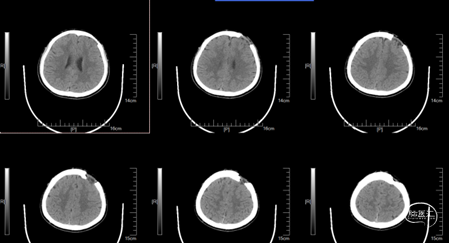

术前CT

入院查体:神志清楚,情感反应、定时定向正常。左侧额部可见颅骨缺损区,骨窗张力不高,原手术切口愈合良好。四肢肌力、肌张力正常。术前头颅CT三维重建清晰显示左侧额部颅骨缺损范围及形态,为个性化植入物的精准设计提供了依据。术前各项检查未见明显手术禁忌。